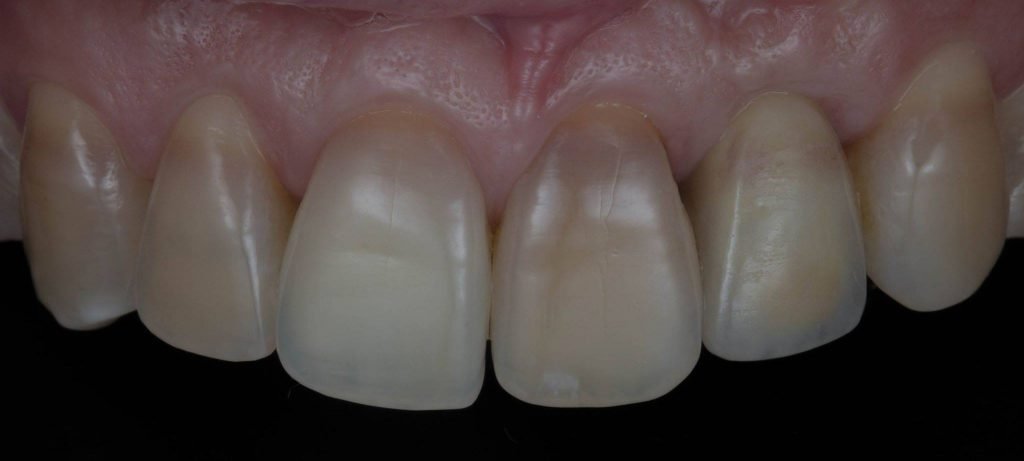

Punto Bajío Casos Clínicos Prótesis Fija sobre Implante unitario Inicio Provisional Final Prótesis Parcial Fija sobre 2 Implantes 2 Implantes Final Prótesis Bucal Removible Inicial Inicial Superior Inicial Inferior Rayos X Inicial Rayos X Inicial Frontal Final Final Superior Final Inferior Prótesis Parcial Fija/ Coronas de Circonio Sonrisa Inicial Foto Inicial Foto Inicial Inferior Foto Final Inferior Foto Final Sonrisa Final Prótesis Total Protesis Inmediatas 1 Protesis Inmediatas 2 Prótesis Removible/ Coronas Metal-Ceramica Carillas Incrustaciones Endodoncia